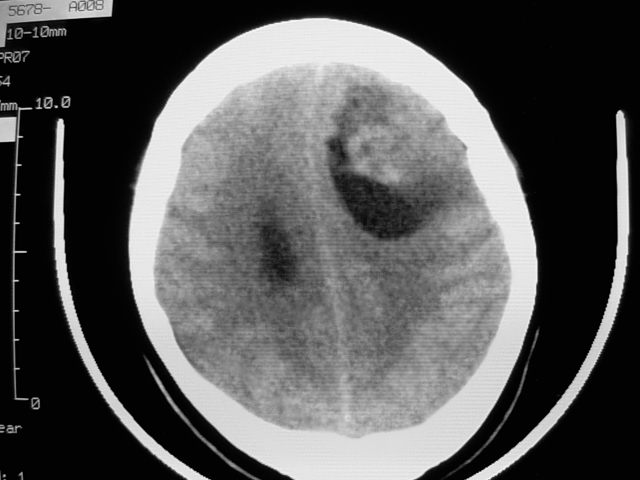

f39y,头疼、眩晕。患者拒绝强化。

左额叶见一巨大椭圆形略低、低密度混杂密度肿块,边界清楚,似与侧脑室额角相通,明显占位效应,左侧侧脑室受压变形,右侧侧脑室扩大,中线结构向右明显弧形移位。鞍上池闭塞。

考虑:1、左额叶良性占位性病变,以皮样囊肿可能性大,伴镰下疝。

肿瘤不再脑室内,左侧的脑室受压了;从平扫考虑两种可能:1.脑膜瘤;2.囊型胶质瘤。

病灶前外侧似可见软组织密度影,考虑囊性星形细胞瘤,建议增强或mr.